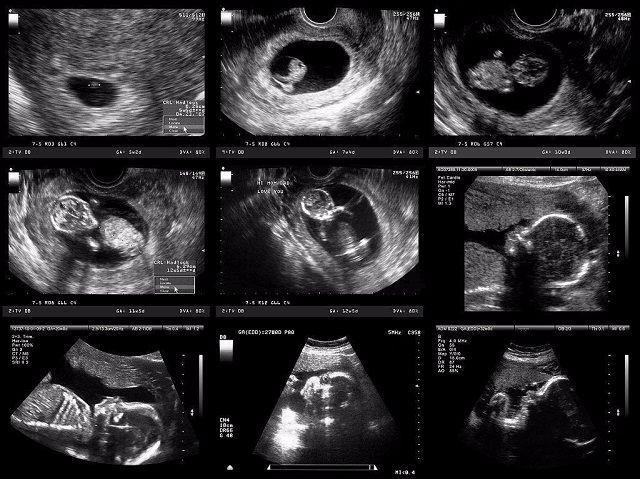

妈妈从孕育到孩子的出生,中间要经历10个月。网上有一组生动形象的动图,可以看出这十个月妈妈究竟经历了什么,这个期间,宝宝每个月在妈妈的肚子里的状态都是不一样的。如果有看过一个胎儿从开始孕育到出生10个月的不同形态,你就会感受到生命的神奇,宝宝在妈妈肚子里每个月不同的形态。

怀孕第一个月

孕妈在刚刚怀孕的时候,宝宝那会儿还只是一个胚胎,被子宫包裹住也就只有鸡蛋那么大。如果孕妈反应激烈,呕吐恶心,这个时期的孕妈是非常难受的。

怀孕第二个月

当宝宝在妈妈肚子里呆到第二个月的时候,胎儿从一个胚胎变成了雏形,而且孕妈的子宫壁也会越来越薄。

怀孕第三个月

这个时候,其实是胎儿发育最快的时期,基本上已经占满了妈妈的整个子宫。孕妈的子宫就会变得很大,还会压迫到膀胱,从这个时候开始就会有尿频的感觉,去厕所次数越来越多,而且肚子也会明显的凸出来。